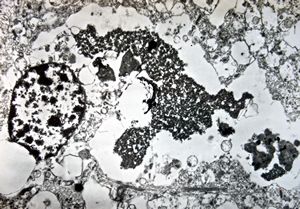

M, | cerebral cortex - malaric pigment

M, | cerebral cortex - malaric pigment

M, | cerebral cortex - malaric pigment

M, | cerebral cortex - malaric pigment